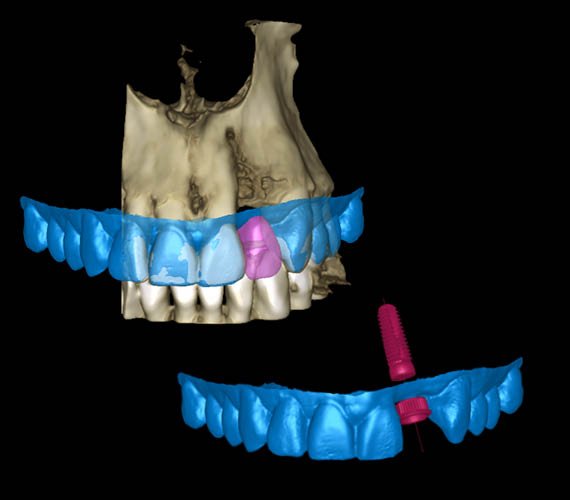

Projektowanie szablonów implantów

Moduł Romexis® Implant Guide umożliwia zaprojektowanie szablonu chirurgicznego w zaledwie kilku krokach. Za pomocą prostego narzędzia lasso, szablon jest projektowany automatycznie na bazie wcześniej zdefiniowanych obszarów. Szablon można wzbogacić dodając wsporniki, okienka szczytowe i wytłoczony tekst lub usuwając wszelkie niepotrzebne materiały. Jeśli ząb został usunięty przed leczeniem implantologicznym, oprogramowanie umożliwia na cyfrowe usunięcie takiego zęba – nie ma więc potrzeby aby ponownie skanować pacjenta.

Szablony spoczywające na błonie śluzowej

Dzięki modułowi Romexis Implant Guide, za pomocą jednego kliknięcia można tworzyć szablony spoczywające na błonie śluzowej. Oprogramowanie automatycznie wykrywa wnętrze protezy i na jego podstawie tworzy szablon. Biblioteka implantów naszego oprogramowania obejmuje również kołki mocujące różnych producentów.